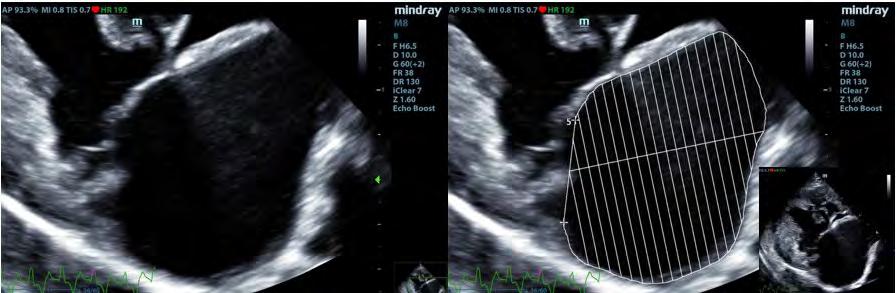

Estudio retrospectivo de 205 pacientes caninos diagnosticados de ECDM mediante ecocardiografía (M8, Mindray, Shenzen) en los que se realizó la ratio LAv/BW utilizando el corte paraesternal derecho longitudinal 4 cámaras y el método monoplano sumatorio de discos (MOD)9 y que, posteriormente, se clasificaron según el consenso para esta enfermedad del Colegio Americano de Medicina Interna veterinaria (ACVIM).7

Se excluyeron del estudio los pacientes con patologías concomitantes a la ECDM, tanto cardíacas como de otros sistemas orgánicos, excepto la presencia de hipertensión pulmonar estimada mediante ecocardiografía. Se realizó la medición del volumen del atrio izquierdo con el método monoplano sumatorio de discos (MOD)9 a partir de la técnica de Simpson, que consiste en la medición del volumen del AI mediante la suma de los volúmenes de diferentes discos contiguos perpendiculares al eje mayor del AI generados por el software del ecógrafo, tras trazar el área del AI y su eje mayor de forma manual. Esta medición se realizó desde el corte paraesternal derecho longitudinal de 4 cámaras en telesístole, previo a la apertura de la válvula mitral (Fig. 1). Se siguió el borde endocárdico del atrio izquierdo, previo a la apertura de la válvula mitral en la telesístole cardíaca, sin incluir las venas pulmonares. Posteriormente, lo correlacionamos con el peso del paciente realizando la ratio: LAv/BW = volumen del atrio izquierdo (ml) / peso del paciente (kg).1,2,6

Figura 1. ECDM. (A) Medida mediante MOD del volumen del AI. (B) Corte paraesternal derecho 4 cámaras, zoom AI. Ratio LA/BW = 3, 8 ml/kg.